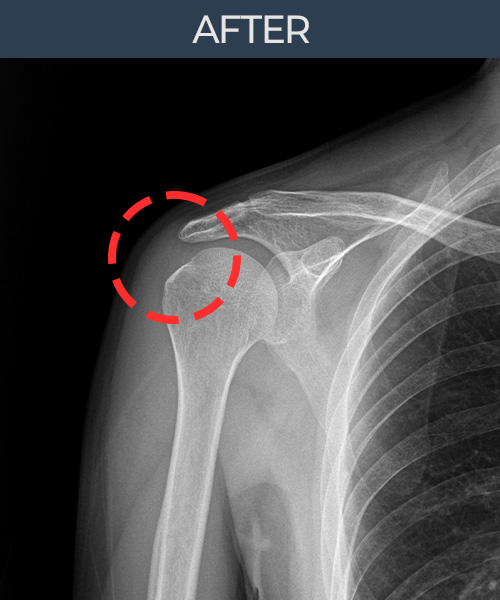

비수술 치료 전후사진

비수술로도 파열된 인대를

물리적으로 재건해 드립니다

플래티넘정형외과에서는 수술없이도 물리적으로

파열된 인대를 재건

하는것이 가능합니다.